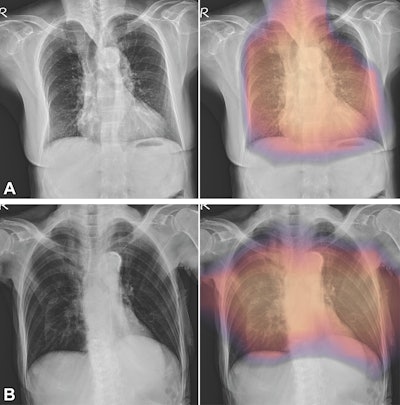

(A, B) Images with true-positive findings. Digital radiographs in (A) a 79-year-old woman with dementia and hypertension and a T-score of −3.4 and (B) an 87-year-old woman with osteoarthritis of the knee and a T-score of −2.7. The AI-enabled chest radiography mainly focused on the vertebrae and ribs around patient’s heart and lung field.Images and caption courtesy of the RSNA.